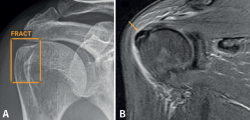

Los falsos positivos corresponden a imágenes patológicas interpretadas como fracturas por la IA pero que, en realidad, se deben a otras patologías que en general son fácilmente identificables: patología degenerativa, fracturas antiguas, calcificaciones (Figura 6), etc. En la valoración de estos falsos positivos es esencial la correlación clínica, valorando si el mecanismo lesional es congruente con la posible fractura señalada y si la clínica es consistente. Como regla general, hay que considerar seriamente la posibilidad de fractura cuando la IA señala una fractura y la sintomatología es coincidente. En algunos casos, la IA señala erróneamente como fracturas algunas imágenes de superposición o debidas a una mala técnica radiográfica.

retla.08115.fs2402001-figura6.png

Figura 6. Tendinopatía calcificante del supraespinoso: radiografía (Rx) anteroposterior de hombro (A) y resonancia magnética (RM) coronal T2 con supresión grasa (B). La inteligencia artificial (IA) señala en la Rx una imagen de fractura (A), que corresponde a una calcificación del supraespinoso, tal y como confirma la RM (B), tratándose por lo tanto de un falso positivo. La RM identifica además una reacción inflamatoria en las partes blandas, indicando una fase reabsortiva, responsable de la sintomatología de la paciente.

Figura 6. Tendinopatía calcificante del supraespinoso: radiografía (Rx) anteroposterior de hombro (A) y resonancia magnética (RM) coronal T2 con supresión grasa (B). La inteligencia artificial (IA) señala en la Rx una imagen de fractura (A), que corresponde a una calcificación del supraespinoso, tal y como confirma la RM (B), tratándose por lo tanto de un falso positivo. La RM identifica además una reacción inflamatoria en las partes blandas, indicando una fase reabsortiva, responsable de la sintomatología de la paciente.